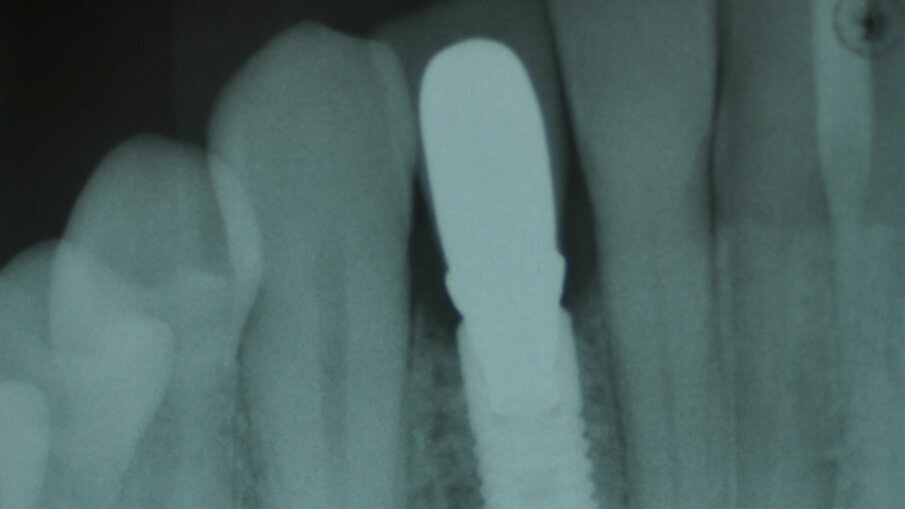

V rámci prvního kroku zavádění implantátu byly pomocí chirurgické šablony vyhodnoceny biologické aspekty podle pravidla 3A-2B (obr. 3). První pozice pro vrtání byla vyznačena tak, aby bylo dosaženo 2B a zajištěn úhel osteotomie pomocí vrtáku Precision Drill EV (Dentsply Sirona). Úhel byl potvrzen a osteotomie v hloubce pro implantát byla preparována pomocí vrtáku Twist Drill EV (Dentsply Sirona; obr. 4). Hloubka osteotomie byla zkontrolována pomocí nástroje Implant Depth Gauge EV (Dentsply Sirona (obr. 5). Poté byl zaveden implantát OsseoSpeed EV 3.6 o délce 11 mm (obr. 6). Předpokladem bylo, že zbývající aproximální kost poskytne oporu aproximální papile. Periapikální RTG snímek pořízený bezprostředně po zavedení implantátu potvrdil, že implantát není v kontaktu s žádným ze sousedních kořenů (obr. 7). Poté byl za použití otiskovací kapny Implant Pick-up Design EV (Dentsply Sirona), což je samonaváděcí otiskovací komponenta, která se umisťuje do implantátu, pořízen otisk, jehož účelem bylo získání informací o pozici implantátu (obr. 8). Provizorní abutment Temporary Abutment EV byl upraven v oblasti krčku tak, aby se zabránilo kontaktu s aproximální kostí a bylo možné správné dosednutí (obr. 9). Za použití kofferdamu pak byla pryskyřicí ihned upevněna provizorní náhrada (obr. 10). Poté byla náhrada sejmuta, dokončena, vyleštěna a za lehkého přitlačení opět nasazena.